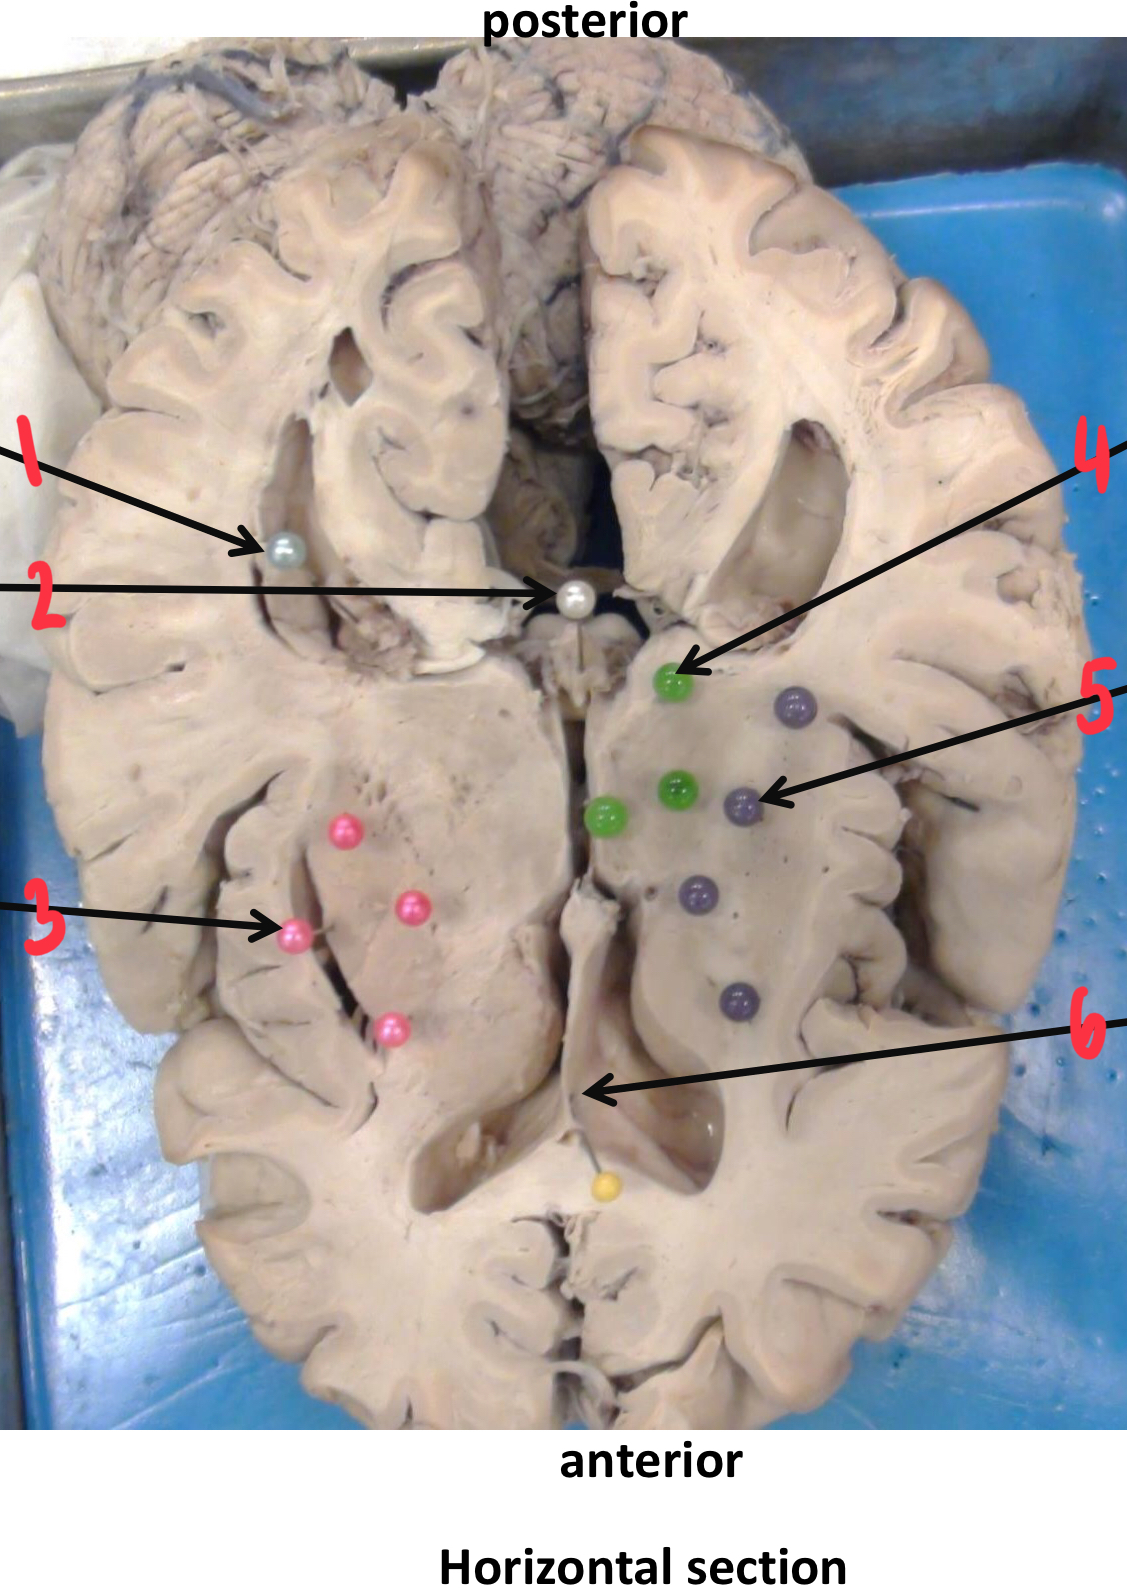

1

putamen

2

hippocampus

3

thalamus

4

internal capsule